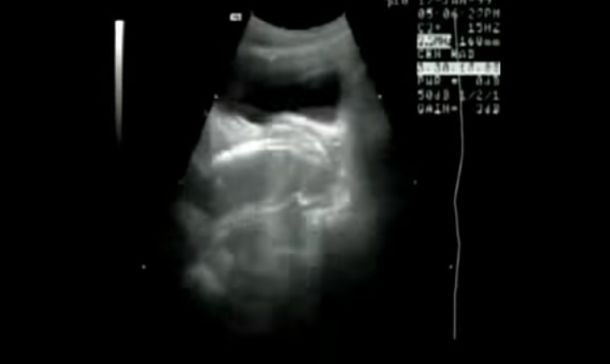

Lo hicieron por la ciencia. Una pareja contribuyó a un experimento médico, que consistía en tener sexo al interior de una máquina de resonancia magnética, para registrar cómo se ve dicha actividad en el escáner, como muestra este video de YouTube.

Las imágenes de YouTube registran los movimientos de una manera similar al de una ecografía. Una persona podría ver una imagen quieta del proceso y podría pensar que se trata de cualquier cosa menos de una pareja teniendo sexo.